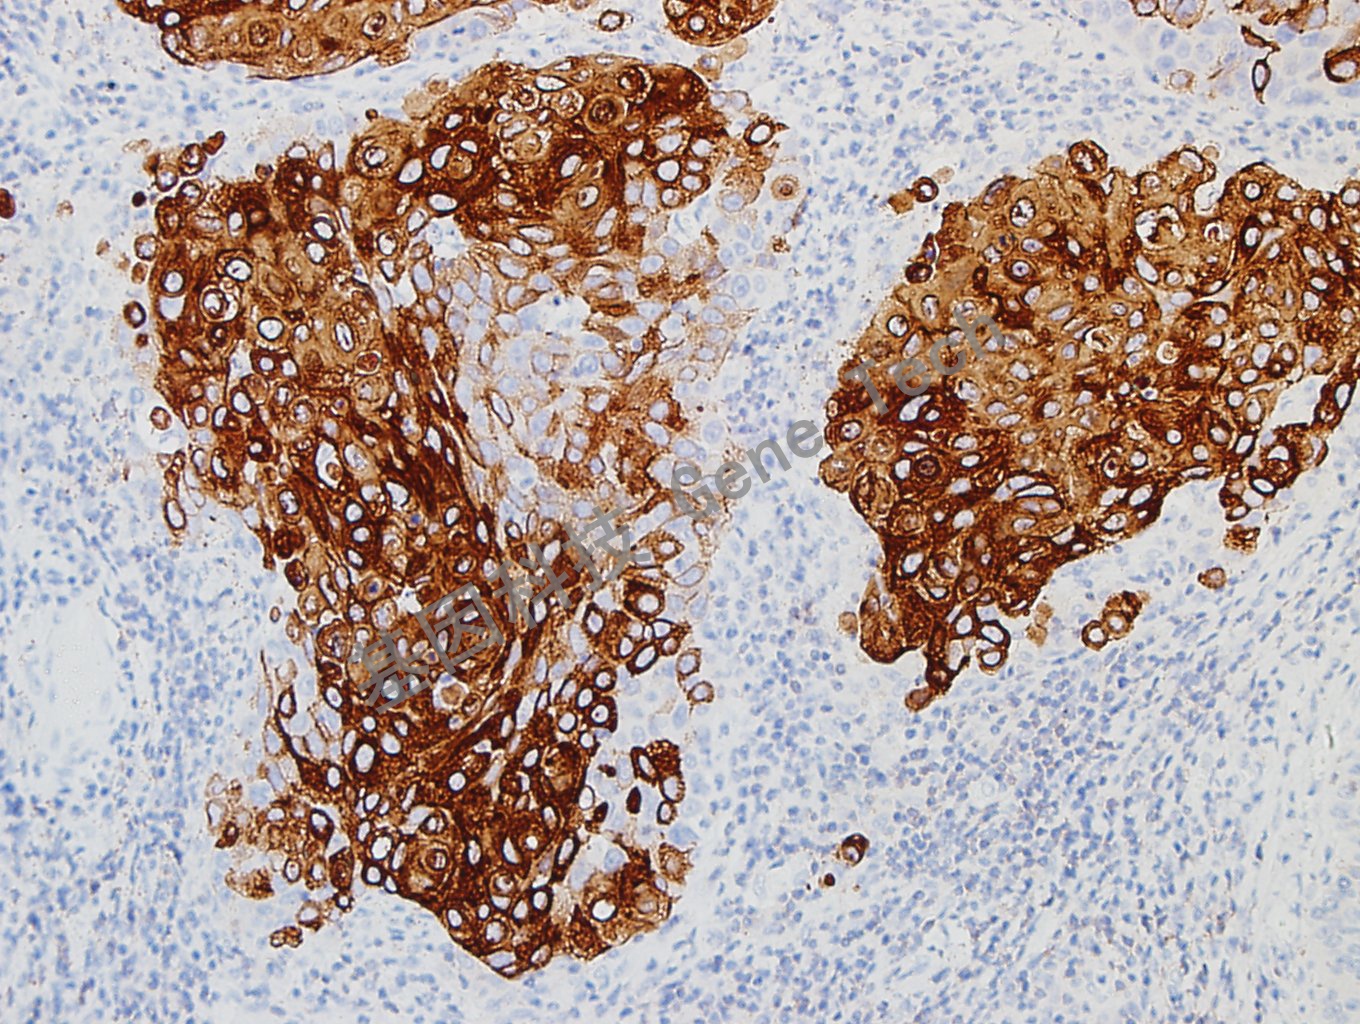

宫颈癌石蜡切片,用CK10/13(GT2341)染色,细胞浆阳性,DAB显色。